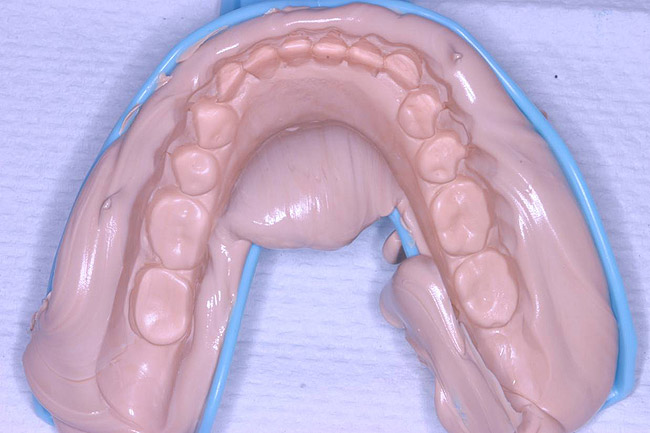

Figure 10  Final upper impression poured up in stone.

Figure 10

The maxillary denture impression was disinfected with antimicrobial spray and walked to the dental laboratory, where it was poured up with yellow stone (Denstone Golden) by the laboratory technician (Figure 10). The case was articulated with the occlusal pin set to replicate centric relation and centric occlusion (Figure 11). The laboratory technician made silicone putty molds (Extrude XP, Kerr Corporation) of the incisal edges of the upper denture. The articulated models were visually examined to ensure proper vertical dimension (Figure 12 and Figure 13). Subsequently, the impression material in the maxillary denture was removed and the denture was cleaned and lightly polished. It was returned immediately to the office, while the patient was waiting in the operatory, to be used as a temporary denture while the final case was completed. The patient was consulted as to preferences regarding teeth shade and shape. VITA Physiodens (Vident, Brea, CA) in Shade A2 were selected for this patient in the attempt to achieve natural-looking, age-appropriate dentition. The patient was dismissed and scheduled to return in 2 weeks for a functional try-in of the new denture.